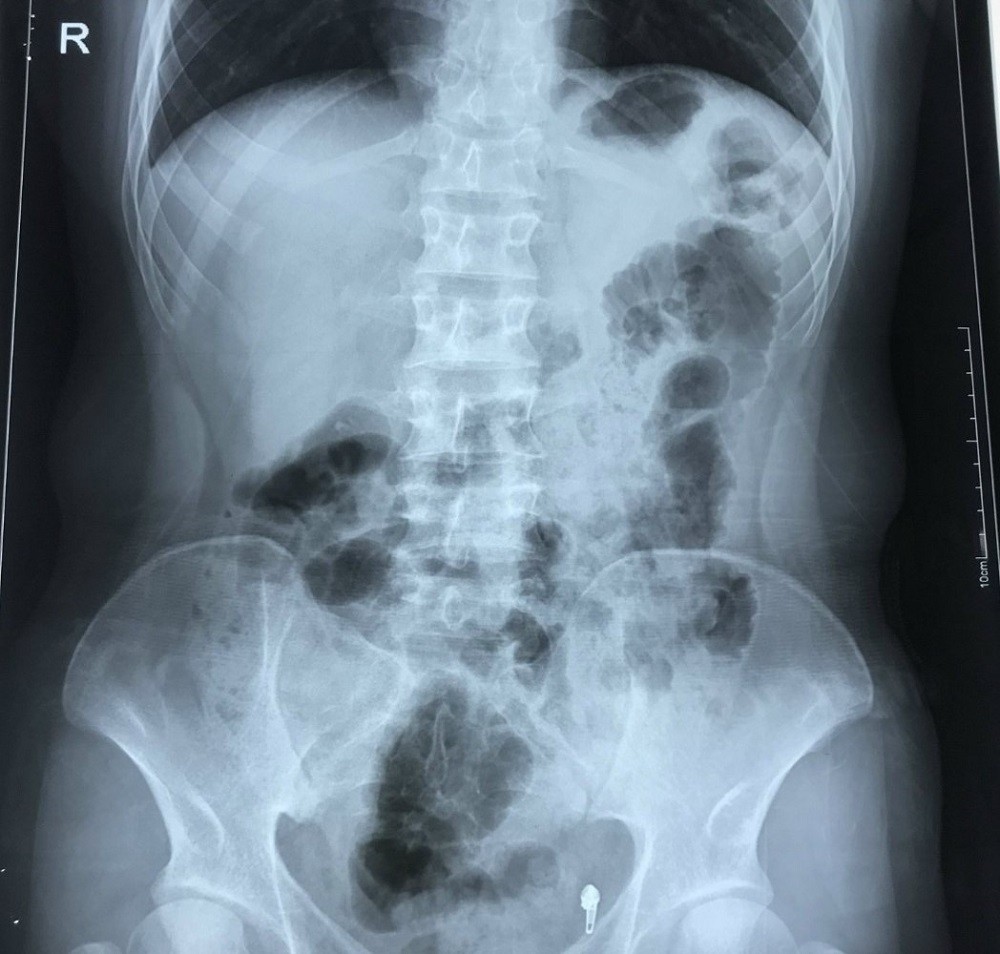

Sau khi siêu âm ổ bụng, chụp X-quang, xét nghiệm máu… bác sĩ chẩn đoán người bệnh bị viêm ruột thừa.

Tuy nhiên, có một điều khiến các bác sĩ rất bất ngờ là trái tim bệnh nhân H. nằm bên lồng ngực phải, ở vị trí đảo ngược so với người bình thường.

| Phim chụp X-quang của bệnh nhân cho thấy tình trạng phủ tạng đảo ngược với trái tim nằm bên lồng ngực phải. Ảnh: BVCC |

Đảo ngược phủ tạng là tình trạng bẩm sinh, trong đó các cơ quan nội tạng trong ngực, bụng bị đảo ngược, phản chiếu theo mặt phẳng đứng dọc so với vị trí bình thường. Các phủ tạng có thể bị đảo ngược hoàn toàn hoặc chỉ một vài cơ quan đơn thuần.

Đây là một dạng dị tật có tính di truyền gen lặn tương đối hiếm gặp, với tỷ lệ 1/10.000 dân, trong đó có khoảng 5-10% có dị tật tim bẩm sinh, còn lại có cuộc sống bình thường, không ảnh hưởng đến sức khỏe.